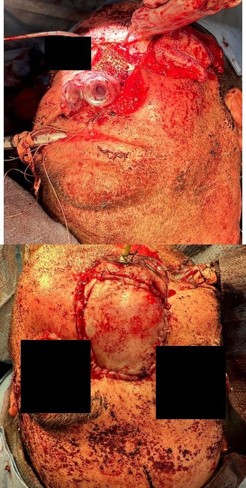

The ostiomeatal complexes were occluded bilaterally, and there was bowing of the nasal septum to the right (Figure 1). He was scheduled for an endoscopic evaluation under anesthesia with nasal biopsy and frozen section analysis. Intraoperatively patient was noted to have fungating masses within bilateral nasal cavities. Multiple biopsies were obtained showing invasive squamous cell carcinoma. The case was terminated and a CT neck with contrast was obtained for surgical planning.

The new CT showed an ulcerated mass within the nasal cavity and a 1.4 cm septal perforation. Fluid and soft tissue were completely opacifying the left maxillary sinus. There was destruction of the nasal bone with the involvement of nasal skin, septal destruction with extension to the hard palate, and an extensive mass inside of the left maxillary sinus without any apparent orbital floor invasion (Figure 2). No cervical or distant metastases were appreciated at the time. The clinical Tumor, Nodal, and Metastasis (TNM) staging for the tumor was noted to be cT4N0M0. We recommended a left maxillectomy, left modified neck dissection with subtotal rhinectomy, and left chimeric scapular free flap for reconstruction.

The procedure began with a left Weber-Ferguson incision. The visible abnormal skin was marked out and removed. This involved 70% of the nasal dorsum extending from the rhinion to the cephalic aspect of the lower lateral cartilages and nasal ala. An intraoral left gingival labial sulcus incision was made extending to the midline of the soft palate and laterally to the gingivobuccal sulcus. The periosteum was elevated with a periosteal elevator, and a reciprocating saw was used to make bony cuts. These were performed through the right lateral nasal bone, junction part between the right maxilla and right nasal bone, and extending into the lower piriform aperture. Another bony cut was made horizontally between the nasal bone and frontal bone superiorly. This was extended to the left medial canthus to include the left orbital medial orbital wall rim and left orbital floor. Lastly, the saw was used along the left anterior maxilla with the intention of removing the maxillary sinus wall completely. Intraoperatively, the tumor was noted to extend into the left parapharyngeal space. Dissection was carried out, staying outside the palpable primary tumor while leaving a sleeve of healthy margin. The bony cuts were then used to cut through the hard palate on the left side and posteriorly separated from the soft palate. No bone cuts were made along the left nasal wall to ensure an en bloc resection. Soft tissue structures were then dissected freely. With the nasal cavity exposed, the saw was used to cut through the hole in the nasal septum. There were multiple defects present, including a skin defect around 6×4 cm, a mucosal defect of 3×4 cm, a left midface defect of 8×6 cm, and a hard palate defect of 6×4 cm. Margins were then carefully obtained and showed no residual tumor. A left modified neck dissection was then performed, and vessels were located for microvascular anastomosis.

A chimeric scapular free flap was chosen for reconstruction because it provides multiple bony components and skin for reconstruction. A 10×2.5 cm segment of the lateral border of the scapula and entire scapular tip was harvested along with the subscapular muscle. The skin paddle obtained was parascapular. The two components of the flap were noted to have two separate arterial origins but shared venous drainage. The flap was then placed into the defect of the face. The bony aspect of the flap was utilized to reconstruct the hard palate and maxillary defect with osteotomies (Figure 3). Proximal scapular bone was plated to the residual hard palate and distal portion to the anterior maxillary process. Two nasal trumpets were placed through bilateral nasal vestibules. The middle portion of the skin paddle was de-epithelialized and used to pack into the nasal cavity. Medpor supported the left orbital contents and was secured to the scapular tip. The scapular tip was affixed to the left zygoma and frontal bone with a reconstruction plate. Then, titanium mesh was used for the nasal bony defect, and the skin paddle’s distal end covered it entirely (Figure 4). The microvascular anastomosis was then performed, drains and nasogastric tube were placed, and incisions were closed. The patient was admitted to the intensive care unit, where hourly flap perfusion checks were performed using a Cook arterial monitoring probe. The patient followed an uncomplicated post-operative course, with discharge on the seventh day.

The patient was seen in an outpatient setting for a two week follow-up and discussion of final pathology results. These showed two masses: ameloblastoma with the invasion of the hard palate, posterior maxilla, and maxillary sinus (Figure 5) as well as a SCC with the cartilaginous and bony invasion of the nasal septum and nasal bone (Figure 6). During this clinic visit, he reported some discharge from one of the incisions and flap edema. He was otherwise doing well, with significant improvements in dysphagia and nasal obstruction. The flap adhered well to native tissue and appeared healthy. The infection cleared up over the next two weeks on a course of antibiotics, and the patient’s nasogastric tube was removed within the following three weeks.